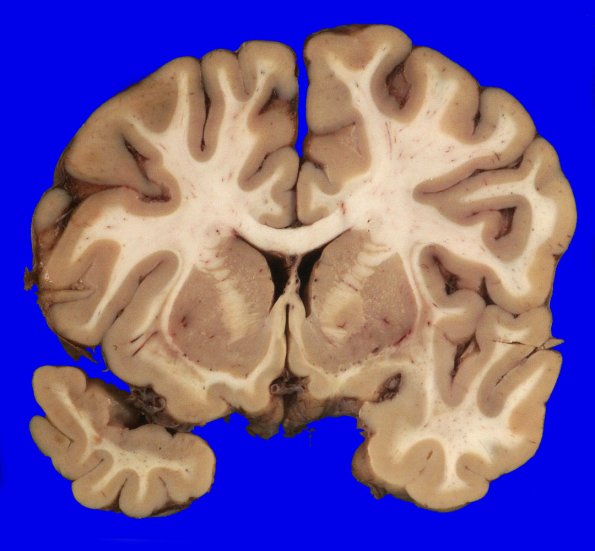

Coronal slicing revealed no significant cortical atrophy or dilatation of the lateral ventricles.